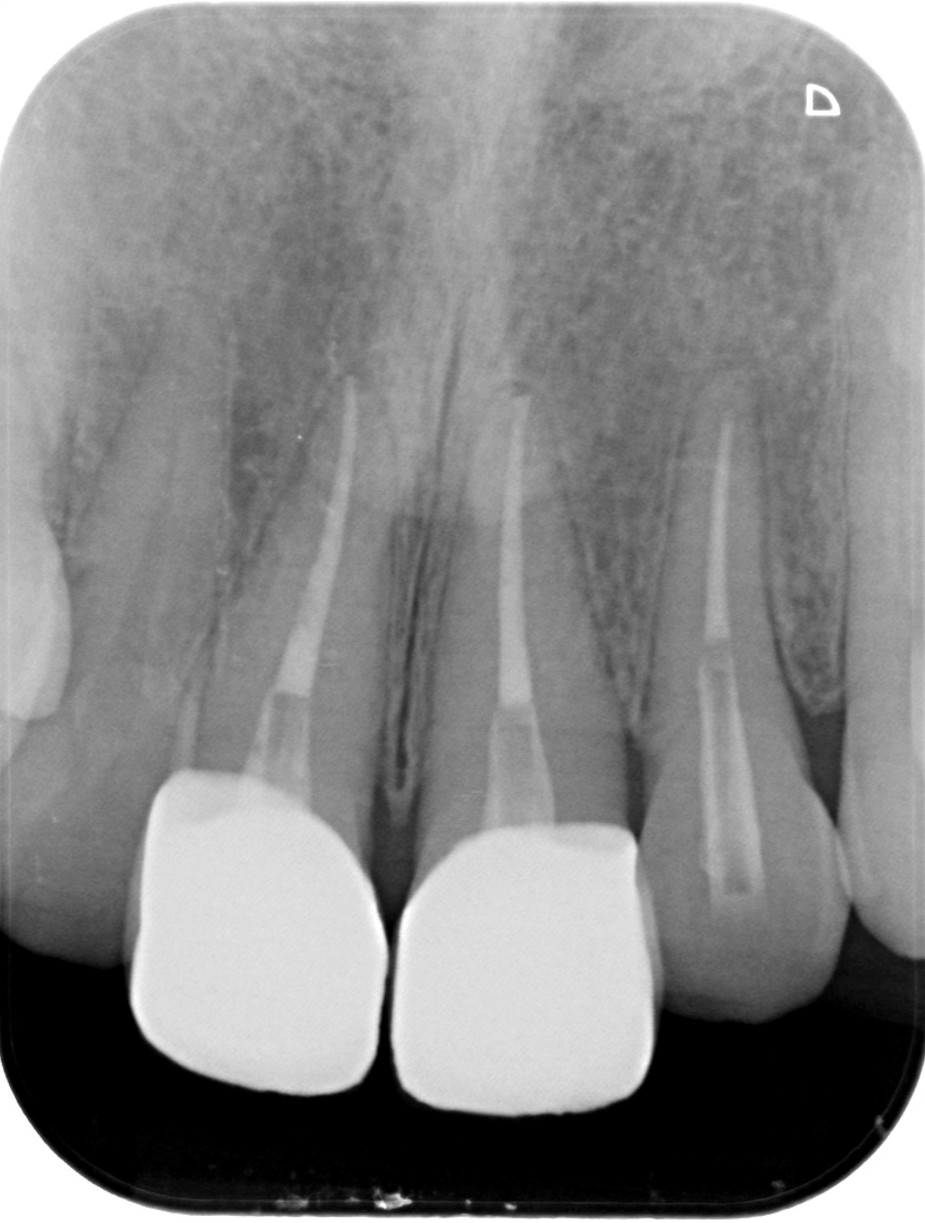

| 医院の診断 | 外傷による歯の亀裂、慢性根尖性歯周炎 |

| 治療費 | 総額:560,000円(税抜) 【内訳】 精密根管治療60,000円(前歯)×3、ファイバーポストコア20,000円×3、セラミック治療160,000円×2 |

| ここがこだわりのポイント!☝ | 外傷で歯の神経が壊死しており、変色歯になっていたので、丁寧に根管治療を行ってからセラミックにて審美性の回復を行なっています。 |